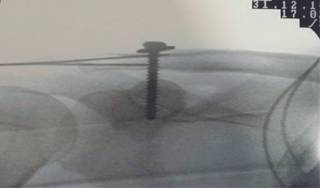

2) Sistema TightRope® acromioclavicular (Arthrex EUA).Es un método de suspensión cortical coracoclavicular descrito por primera vez en 2007,16 está formado por dos pastillas metálicas unidas por un sistema de suturas resistentes específicas de la marca. Puede realizarse por control fluoroscópico o por artroscopia, siendo la segunda más ventajosa debido a que se observa directamente la posición de la pastilla coracoidea y con menos posibilidades de falla del implante. Es importante aclarar que en nuestra institución se realiza de manera abierta (Figura 2).

Figura 2: Radiografía AP hombro postquirúrgica inmediata de técnica de TightRope® acromioclavicular.